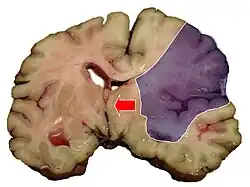

Midline shift

Midline shift is a shift of the brain past its center line.[1] The sign may be evident on neuroimaging such as CT scanning.[1] The sign is considered ominous because it is commonly associated with a distortion of the brain stem that can cause serious dysfunction evidenced by abnormal posturing and failure of the pupils to constrict in response to light.[1] Midline shift is often associated with high intracranial pressure (ICP), which can be deadly.[1] In fact, midline shift is a measure of ICP; presence of the former is an indication of the latter.[2] Presence of midline shift is an indication for neurosurgeons to take measures to monitor and control ICP.[1] Immediate surgery may be indicated when there is a midline shift of over 5 mm.[3][4] The sign can be caused by conditions including traumatic brain injury,[1] stroke, hematoma, or birth deformity that leads to a raised intracranial pressure.